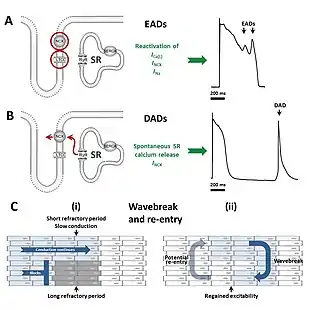

Andersen–Tawil syndrome increases the risk of abnormal heart rhythms by disturbing the electrical signals that are used to coordinate individual heart cells. The genetic mutation disturbs an ion channel responsible for the flow of potassium, reducing the /K1 current. This prolongs of the cardiac action potential – the characteristic pattern of voltage changes across the cell membrane that occur with each heart beat, and depolarises the resting membrane potential of cardiac and skeletal muscle cells.[4]

Cardiac and skeletal muscle cells, when relaxed, have fewer positively charged ions on the inner side of their cell membrane than on the outer side, referred to as their membranes being polarised.[8] The main ion current responsible for maintaining this polarity is /K1, and a decrease in this current leads to less polarity at rest, or a depolarised resting membrane potential. When these cells contract, positively charged ions such as sodium and calcium enter the cell through ion channels, depolarising or reversing this polarity. After a contraction has taken place, the cell restores its polarity (or repolarises) by allowing positively charged ions such as potassium to leave the cell, restoring the membrane to its relaxed, polarised state.[8] The genetic mutation found in those with Andersen–Tawil decreases the flow of potassium, slowing the rate of repolarisation which can be seen in individual cardiac muscle cells as a longer action potential and on the surface ECG as a prolonged QT interval.[4]

The prolonged action potentials can lead to arrhythmias through several potential mechanisms. The frequent ventricular ectopy and bidirectional VT typical of Andersen–Tawil syndrome are initiated by a triggering beat in the form of an afterdepolarisation. Early afterdepolarisations, occurring before the cell has fully repolarised, arise due to reactivation of calcium and sodium channels that would normally be inactivated until the next heartbeat is due.[9] Under the right conditions, reactivation of these currents can cause further depolarisation of the cell, facilitated by the sodium-calcium exchanger.[9] Early afterdepolarisations may occur as single events, but may occur repeatedly leading to multiple rapid activations of the cell.[9] Delayed afterdepolarisations, occurring after repolarisation has completed, arise from the spontaneous release of calcium from the intracellular calcium store known as the sarcoplasmic reticulum. This calcium release then leaves the cell through the sodium calcium exchanger in exchange for sodium, generating a net inward current and depolarising the cell membrane.[9] If this transient inward current is large enough, a premature action potential is triggered.